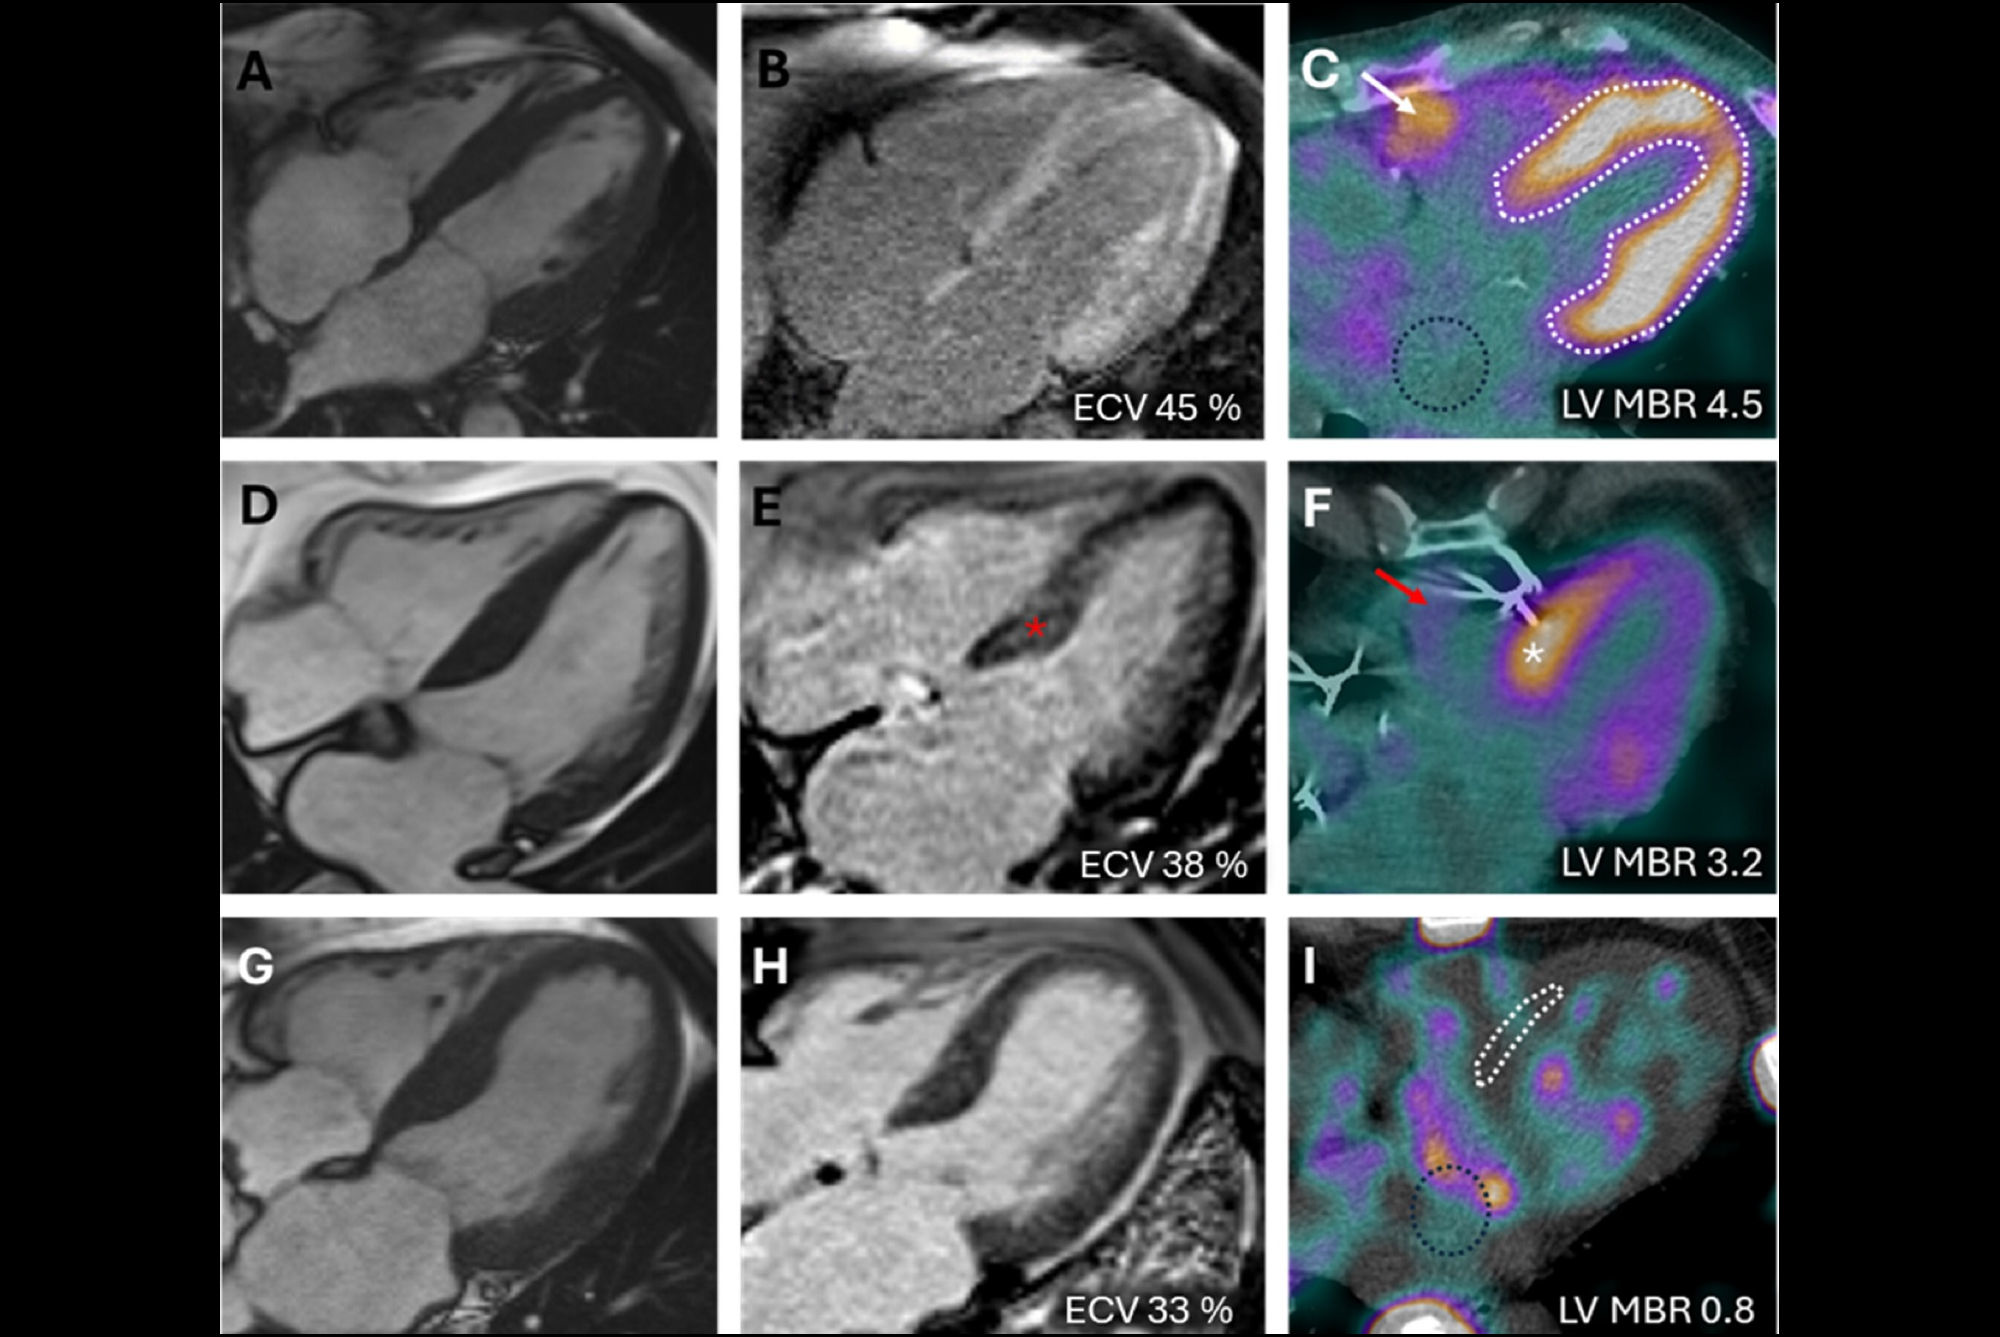

I-124 evuzamitide PET/CT images of a patient with light-chain amyloidosis showing a decrease in amyloid load and organ volume on follow-up.Image courtesy of the American Society of Nuclear Cardiology

According to the analysis, the mean time between imaging was 2.9 years. An increase in cardiac uptake was observed in three patients with ATTR amyloidosis and in only one with AL amyloidosis. For the entire population, there was a significant correlation between the change in cardiac tracer uptake and change in serum NTproBNP (Spearman rank correlation coefficient [rs] = 0.62, p = 0.005).

In addition, significant correlations were observed between cardiac I-124 evuzamitide uptake and left ventricle wall thickness (Pearson correlation coefficient [rP] = 0.71, p = 0.0007), and global longitudinal strain (rP = 0.47, p = 0.043). The researchers observed decreases in hepatosplenic amyloid load and organ volume in two of the AL patients.